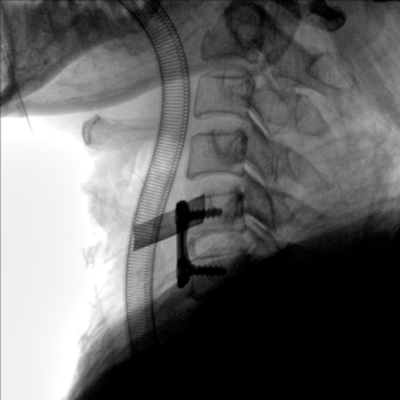

臨床適用科室:骨科、普通外科、矯形外科、創傷外科、泌尿外科、脊柱外科、疼痛外科、消化科、婦科等科室。

大尺寸動態平板探測器,高DQE、低噪聲、圖像清晰。采用多分辨率圖像增強處理技術,不同部位不同圖像處理算法,滿足客戶多樣化的需求。

采用智能變頻脈沖透視技術,優化圖像質量的同時降低輻射劑量,呵護醫患健康